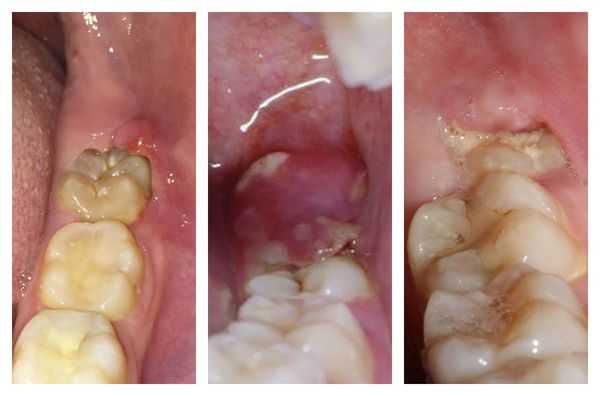

Если пациент своевременно не обратился к врачу, то перикоронит переходит в хроническую форму. Симптомы болезни притупляются из-за оттока воспалительного экссудата, но в действительности процесс воспаления распространяется на мягкие ткани, окружающие причинный зуб.

При хронической перикороните наблюдается слабо выраженное покраснение десны. Образуется серозный или, как правило, гнойный экссудат, который сопровождается неприятным запахом изо рта. В поднижнечелюстной области с поражённой стороны можно нащупать воспалённые регионарные лимфоузлы. Эти симптомы сопровождаются болью при открывании рта.

Острая форма характеризуется резким началом, быстрым развитием воспаления и яркими симптомами, в частности острой болью в месте прорезывания. Пациенту становится больно и/или трудно открывать рот. При несвоевременном обращении данная форма может перейти в хронический перикоронит.

Хроническая форма протекает менее остро. Болевые ощущения не выражены. Наблюдается небольшое покраснение и отёк мягких тканей. Общее состояние удовлетворительное. Лимфатические узлы увеличены, но незначительно. Возможен неприятный запах изо рта.

Катаральная форма — начальная стадия болезни, которая может перерасти в язвенный или гнойный перикоронит. Сопровождается болевыми ощущениями, которые усиливаются во время еды. Нависающий край десны воспалён, при пальпации вызывает боль. Региональные лимфоузлы на стороне поражения воспаляются, увеличиваются, становятся болезненными при пальпации. Гнойных выделений из-под капюшона нет. Открывание рта не затруднено. При своевременном лечении быстро проходит вместе с сопутствующими симптомами.

Язвенная форма . Развивается при разрушении мягких тканей на фоне воспаления. Отличается образованием язв на слизистой оболочке вокруг причинного зуба. При попытке удалить образовавшийся налёт возникает боль.

Гнойная форма — одна из самых тяжёлых форм перикоронита. Больной выглядит измученным, о бщее состояние резко ухудшается. Наблюдается стойкое повышение температуры до 38,0 °С , резкая боль при глотании и открывании рта, иррадиация в ухо или висок. Из причинной области в полость рта выделяется гной, причём при пальпации количество отделяемого и болезненные ощущения усиливаются. Регионарные лимфоузлы увеличены и подвижны. Отекает и краснеет не только капюшон и десна, но и нёбно-язычная дужка, слизистая щеки и мягкое нёбо [8] [13] .